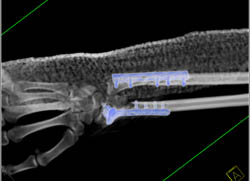

Failed Pectus Repair